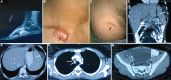

The patient, a 14 yr old male, had disseminated Mycobacterium intracellulare infection; no immune defect could be detected. He was successfully treated. (A) The magnetic resonance imaging scan shows osteomyelitis of foot bone (black arrow). (B) Black arrow shows healing of cutaneous lesion by keloid formation. (C) Upper part of thigh shows another healed skin lesion (black arrow). (D and E) Hypodense lesions in the spleen (white open circles) and peri-splenic abscess (white arrows). (F) Bilateral conglomerate necrotic axillary (extreme-left and -right arrows) and right paratracheal lymph nodes (long and short arrows in the centre of CT image), calcification is also noted in the lymph nodes. (G) Iliopsoas abscess on the right side (white asterisk). Source: Reproduced with permission from Ref. .